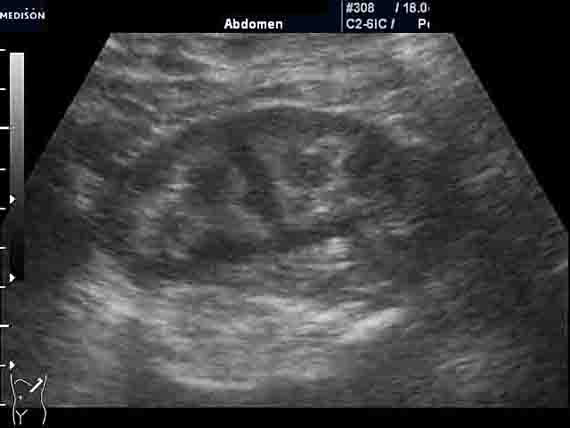

Женщина 50 лет. Прооперирована месяц назад по поводу альдостеромы левого надпочечника. Плановое УЗИ почек и надпочечников после операции. У нас смотрится впервые.

На УЗИ выявляю изменения в почках - см. фото. Паратгормон и уровень мочевой кислоты в норме. Креатинин 100-110. Меня старательно уверяют, что почки нормальные. И на МРТ, сделанной перед операцией, почки были якобы не изменены (но снимки потеряли). Отправил пациентку за копией снимков (в "живом" или цифровом варианте). Но большой надежды на восстановление данных нет.

Как вам кажется, коллеги: это нормальные почки? Я не исключаю в т.ч. и один из вариантов "губчатой почки".

Левая почка.

Сонографическая картина нефрокальциноза. В некоторых пособиях такую картину называют "почками Андерссон-Карра".